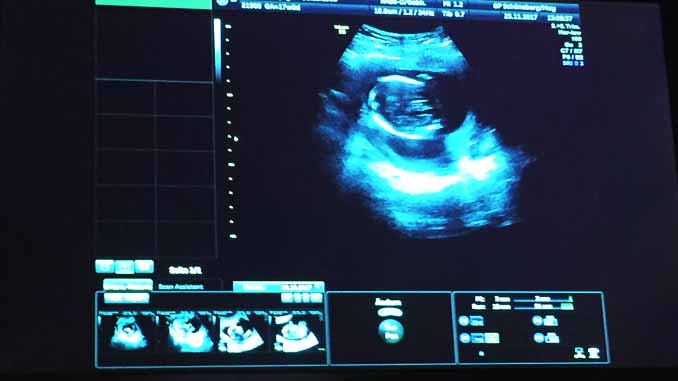

Để chẩn đoán bệnh, thai phụ được lấy máu xét nghiệm từ tuần 11 và 13 của thai kì, đồng thời được siêu âm độ mờ da gáy. Nếu độ mờ da gáy trên 3mm, thai nhi sẽ có nguy cơ bị một số bệnh bất thường về nhiễm sắc thể, trong đó có hội chứng Down.